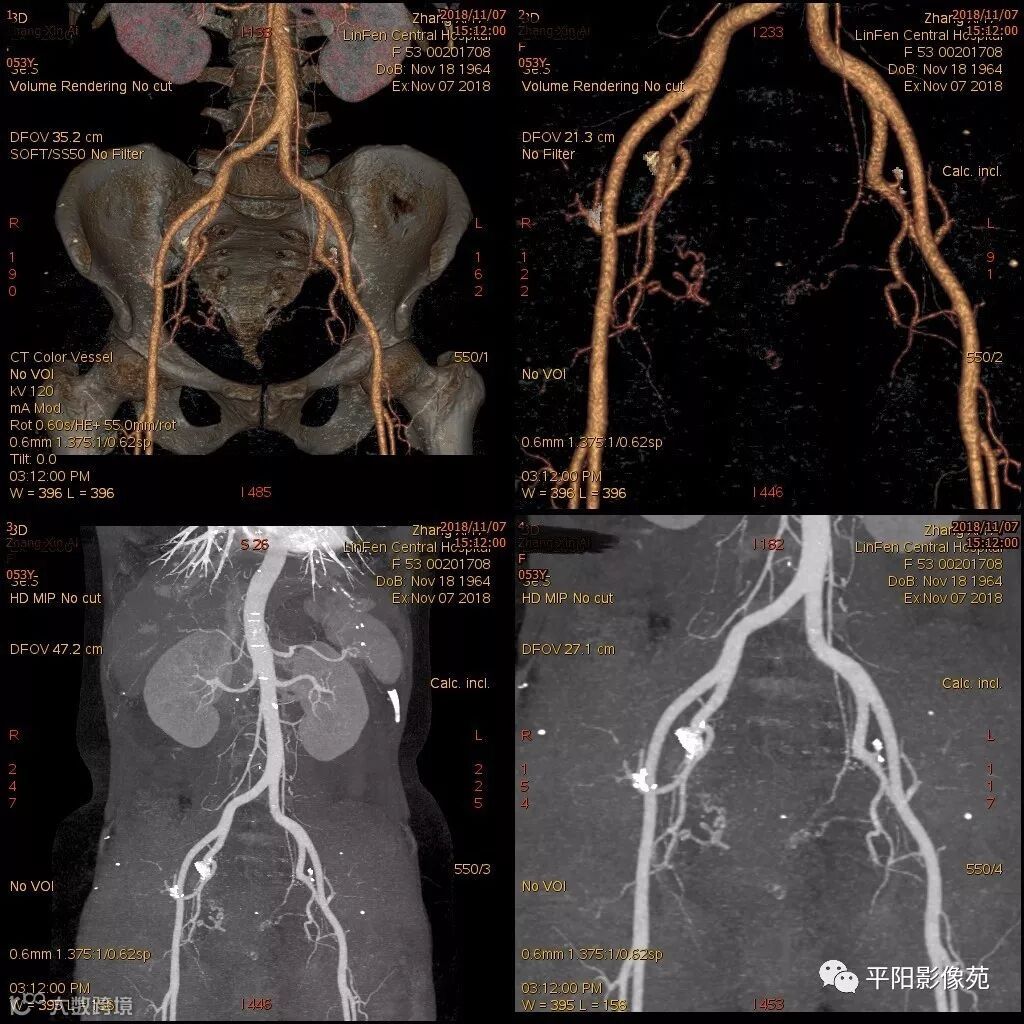

影像特点

右附件区薄壁囊性病变,壁明显强化,边界不清,供血动脉源自子宫动脉,且局部动脉血管增多;其内侧可见卵圆形无强化囊性病灶。

附件区病变多见于卵巢,以囊性为主的病灶多为卵巢囊肿、粘液/浆液性囊腺瘤、皮样囊肿等,这些病灶都具有鲜明瘤体结构,且壁强化多为轻-中度,供血动脉多源自卵巢动脉;而本例患者右附件区薄壁囊性病灶,多位置观察形态为迂曲管状,且壁有明显延迟强化,供血动脉源自子宫动脉,较对侧血管丰富,故而考虑源自输卵管或子宫病变,但子宫发生的薄壁囊性病变较少,多见于子宫肌瘤囊变,完全囊变者少见,且形态轮廓与肌瘤相同为球形故而排除,结合患者腹痛前有感冒病史,且有压痛,因此考虑输卵管积脓可能。其内侧无强化囊性肿块,考虑卵巢囊肿可能。

主要与卵巢囊肿伴感染、皮样囊肿、卵巢囊腺瘤等鉴别,当病变表现相似时,可根据供血动脉以兹鉴别,卵巢病灶为卵巢动脉供血,其自腹主动脉,输卵管病变多由输卵管动脉供血,源自髂内动脉→子宫动脉→输卵管动脉。